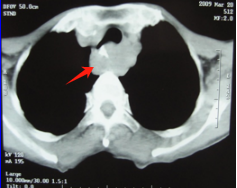

治疗前 病灶占据整个食管管腔 治疗后 食管病灶已完全消失

针对王大爷的病情及王先生的疑虑,医院组织放疗科、肿瘤内科专家为其会诊,详细解释了放疗的治疗原理、流程和反应,彻底打消了王先生的顾虑,王先生为父亲选择了“根治性精准放射治疗+局部热疗”的治疗方案。经过一个多月的放疗,王大爷吞咽越来越顺畅,饭量逐渐恢复到正常,体重也增加了。治疗中期复查CT,病灶缩小了一大半,这更加坚定了他们战胜病魔的信心。放疗结束后,王大爷还在医生的鼓励下,做了4个周期的全身化疗巩固。今天是他们返院复查的日子。